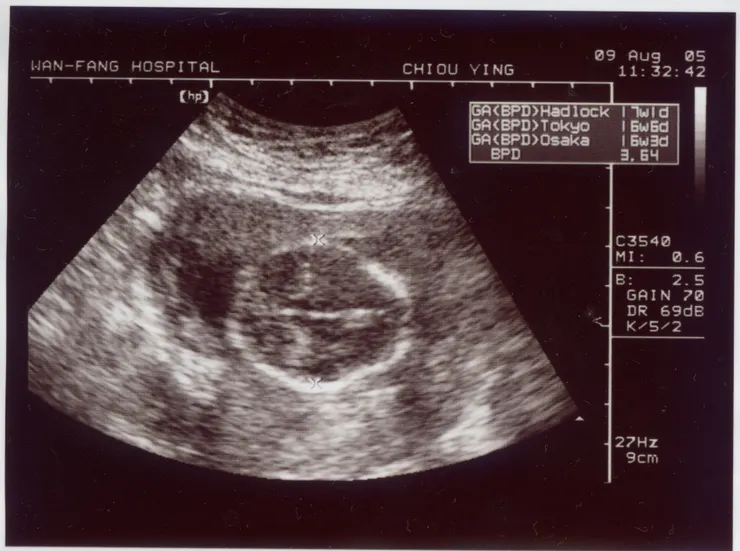

接著,我再到超音波室去照超音波。照超音波的時候,那個女技術士一直在量小朋友的頭圍,照阿照的,我看到小朋友動了一下,閃開來!我問女技術士:「聽說超音波照太多對小朋友不好?」

量好了頭圍,我再拿著超音波照等候進診間看醫生。

輪到我的時候,醫生看著小朋友的超音波照跟我解釋,小孩子的頭圍是4.62,正常。還告訴我,孕婦要多運動,最好的運動是游泳。他還一邊跟其他的孕婦說:「你們都有聽到厚?游泳是孕婦最好的運動!」哇!這真是個活潑的醫生!